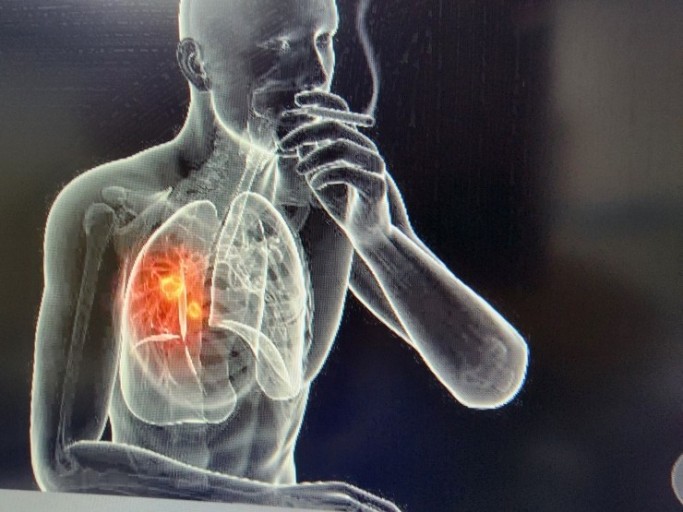

폐암 초기증상 4. 기침

폐암 초기증상 다음은 기침입니다. 이것은 호흡곤란과 이어지는 증상인데요. 기침은 가장 흔하게 발생하는 폐암 초기증상입니다. 기침 사실 감기나 천식, 최근에는 코로나 증상 등의 다른 호흡기 질병에서도 흔히 발생하는 증상이라 처음에는 대수롭지 않게 여기고 넘어가는 그럴 경우가 많습니다. 하지만 계속하여 기침 증상이 끊이지 않는다면 폐암 체크를 받아보는 게 좋습니다.